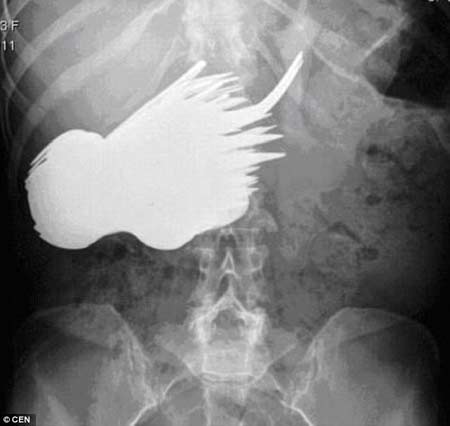

สำนักข่าวต่างประเทศรายงานเมื่อวันที่ 29 ตุลาคม ว่า เกิดการเปิดเผยกรณีประหลาด นางมากาเร็ต ดาอัลแมน วัย 58 ปี ถูกนำตัวส่งโรงพยาบาล ภายหลังเกิดอาการปวดท้อง ก่อนที่แพทย์จะต้องตกตะลึง เมื่อเอ็กซ์เรย์พบช้อน-ซ้อม จำนวน 78 คัน ทำให้แพทย์ต้องนำตัวเธอเข้าห้องผ่าตัด เพื่อผ่าออกช้อนส้อมจำนวนมากดังกล่าวออกจากกระเพาะเธอทีละคัน

รายงานระบุว่า การเปิดเผยดังกล่าวมีขึ้นในวารสารการแพทย์ของเนเธอร์แลนด์ ซึ่งเหตุการณ์นี้เกิดขึ้นเมื่อ 30 ปีก่อน แต่เพิ่งถูกนำมาเปิดเผยเมื่อสัปดาห์ที่ผ่านมา โดยแพทย์เจ้าของไข้เปิดเผยว่า หญิงดังกล่าวดูเหมือนจะป่วยมีอาการจิตใจถูกครอบงำ และทุกครั้งที่เธอนั่งเพื่อกินอาหาร ก็จะเกิดอาการไม่อยากกินอาหาร แต่กินช้อนส้อมแทน และขณะที่เธอเข้ารับการผ่าตัด เธอบอกว่า เธอไม่รู้ว่าทำไมตัวเองจึงเกิดอาการอยากกินช้อนส้อม โดยเธอไม่สามารถบังคับตัวเองได้

ด้านแพทย์หลายคนบอกว่า หญิงผู้นี้ได้รับการวินิจฉัยว่า ป่วยมีพฤติกรรมประหลาดที่ทำให้มีความอยากกระหายจะกินช้อนและส้อม อย่างไรก็ตาม เธอไม่เคยกินมีดเข้าท้อง ซึ่งเจ้าตัวก็ไม่รู้เหตุผลว่าเพราะอะไร